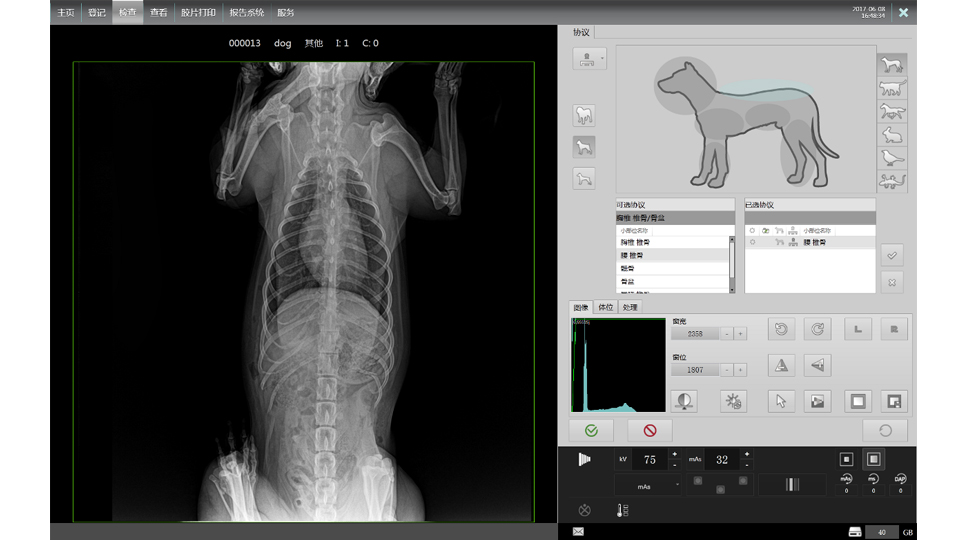

● 17*17大尺寸平板探测器,获得高质量图像

● 优异的空间分辨率及信噪比,提升图像质量

● 采用线噪声消除技术,使成像质量提升40%

● 进口高品质球管,大功率、高热容量、微焦点,1.0/2.0mm双焦点设计

● 25kHz高主逆变频率,输出电压更稳定;瞬时定格影像,无拖尾现象

● 智能高效的图像处理软件,大幅提升图像质量

● 可浮动床面设计,满足大部分中小型宠物检查

● 灵巧机架设计,近台操作,手动/遥控曝光,结构灵活紧凑